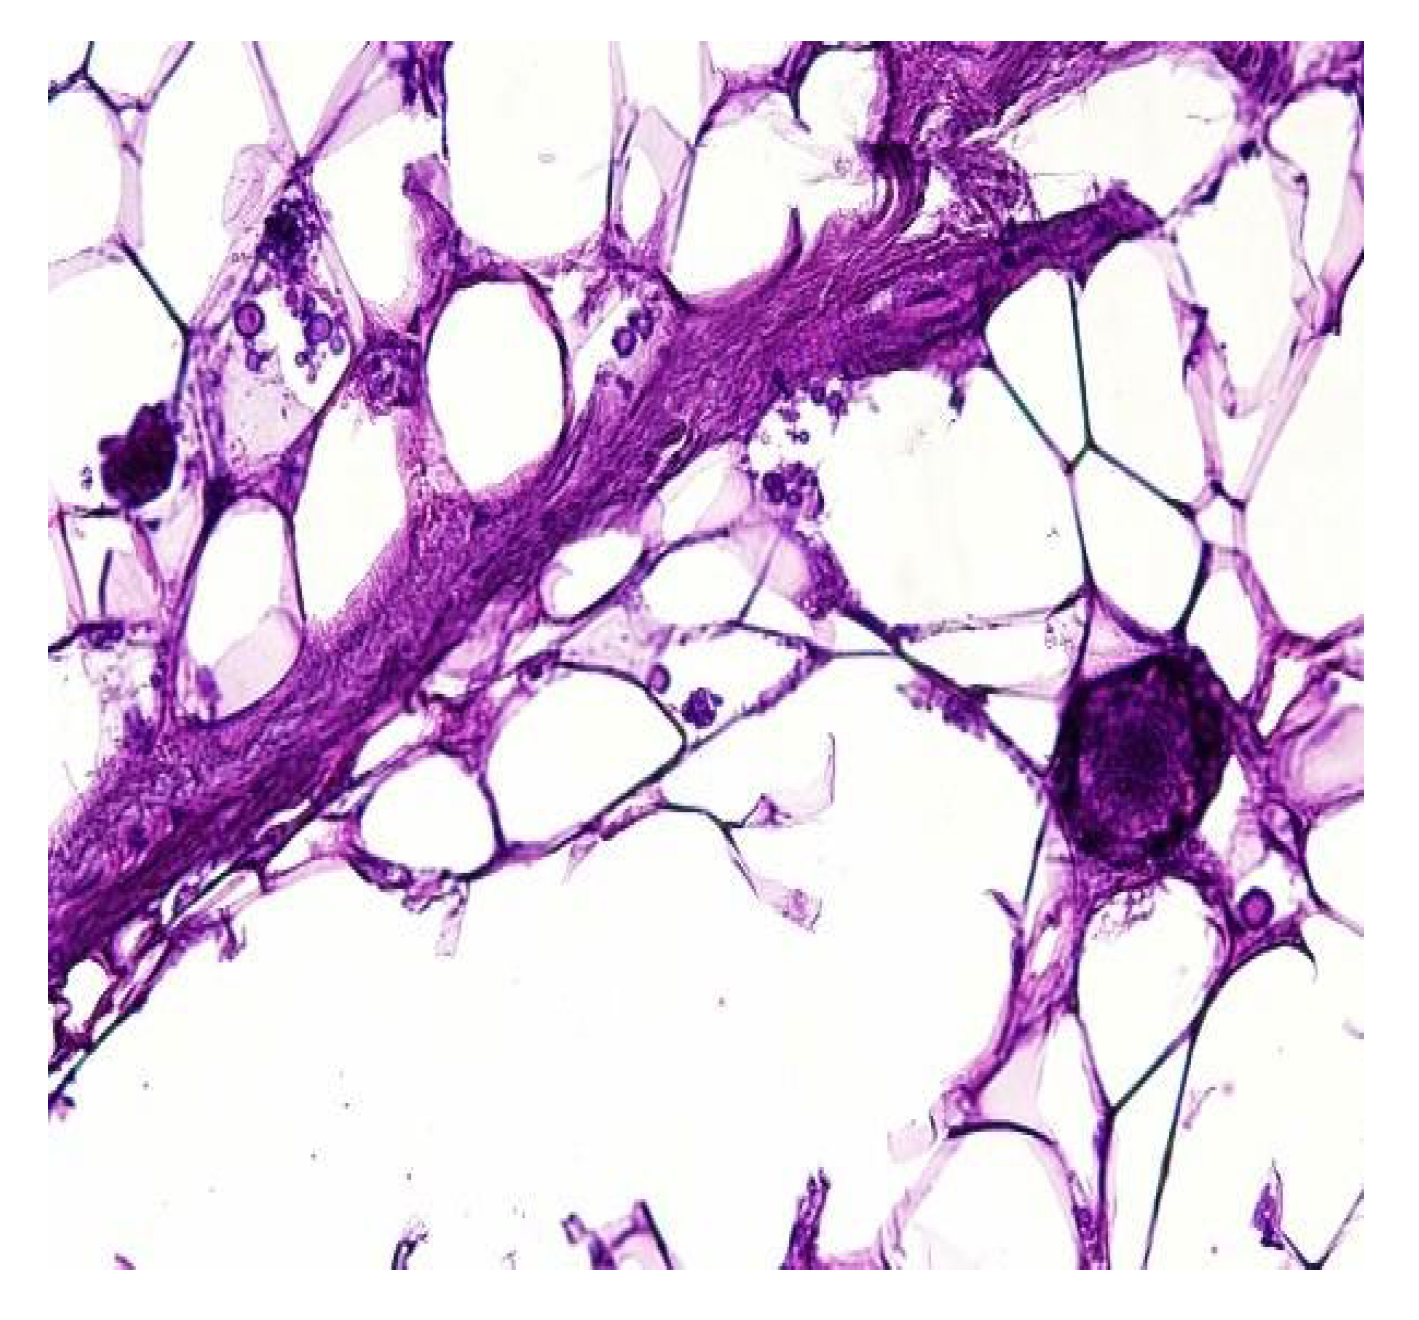

In both of the described cases, optical microscopy revealed lamellar fibrosis, deposits of fibrin on the surface of the peritoneum (Figure 3 and Figure 4) and dystrophic calcifications in the peritoneum (Figure 5 and Figure 6).

Several studies have attempted to identify and/or standardize the morpho-pathological changes in EPS, differentiating it from PS, which is a common occurrence in patients receiving PD and presents as a simple sclerosis [12,13,22,34,35]. The most frequent aspects observed were fibrin deposits, fibroblast swelling and mononuclear cell infiltration [11,12,22]. Garosi et al. investigated 39 biopsies from patients with EPS and found that tissue and arterial calcification, the thickening of the submesothelial layer and vasculopathy were the most significant observed changes [30]. In another study, Sherif et al. found that only fibrin deposits and the thickening of the compacta were significant [36]. In the present study, lamellar fibrosis, decreased cellularity, low grade perivascular inflammation and dystrophic peritoneal calcifications were frequent histological changes. Similarly, Braun et al. attempted to standardize the lesions and to define reproducible histological parameters in patients with EPS. It was found that calcification was a highly indicative criteria for EPS. Furthermore, mesothelial denudation, chronic inflammation, fibrin deposits, decreased cellularity and the presence of fibroblast-like cells were also indicative of EPS [10].

Figure 4. Lamellar fibrosis, condensed fibrin on the surface of the peritoneum and decreased cellularity (hematoxylin and eosin staining, original magnification × 100).